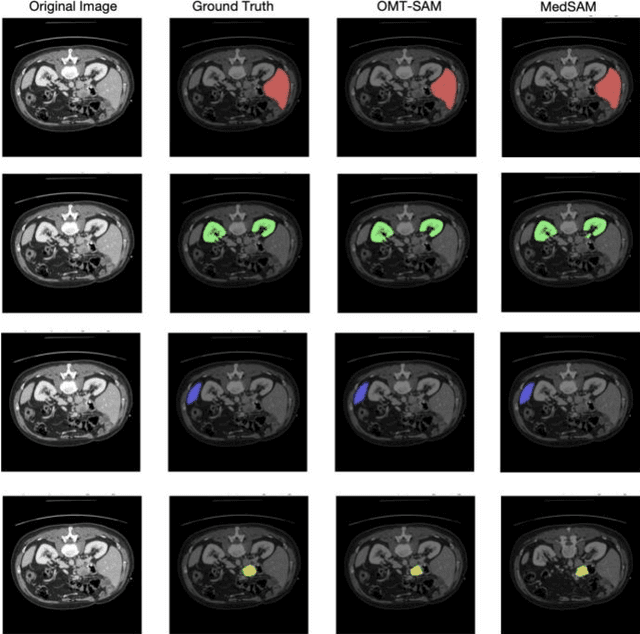

Abstract:Accurate segmentation is essential for effective treatment planning and disease monitoring. Existing medical image segmentation methods predominantly rely on uni-modal visual inputs, such as images or videos, requiring labor-intensive manual annotations. Additionally, medical imaging techniques capture multiple intertwined organs within a single scan, further complicating segmentation accuracy. To address these challenges, MedSAM, a large-scale medical segmentation model based on the Segment Anything Model (SAM), was developed to enhance segmentation accuracy by integrating image features with user-provided prompts. While MedSAM has demonstrated strong performance across various medical segmentation tasks, it primarily relies on geometric prompts (e.g., points and bounding boxes) and lacks support for text-based prompts, which could help specify subtle or ambiguous anatomical structures. To overcome these limitations, we propose the Organ-aware Multi-scale Text-guided Medical Image Segmentation Model (OMT-SAM) for multi-organ segmentation. Our approach introduces CLIP encoders as a novel image-text prompt encoder, operating with the geometric prompt encoder to provide informative contextual guidance. We pair descriptive textual prompts with corresponding images, processing them through pre-trained CLIP encoders and a cross-attention mechanism to generate fused image-text embeddings. Additionally, we extract multi-scale visual features from MedSAM, capturing fine-grained anatomical details at different levels of granularity. We evaluate OMT-SAM on the FLARE 2021 dataset, benchmarking its performance against existing segmentation methods. Empirical results demonstrate that OMT-SAM achieves a mean Dice Similarity Coefficient of 0.937, outperforming MedSAM (0.893) and other segmentation models, highlighting its superior capability in handling complex medical image segmentation tasks.